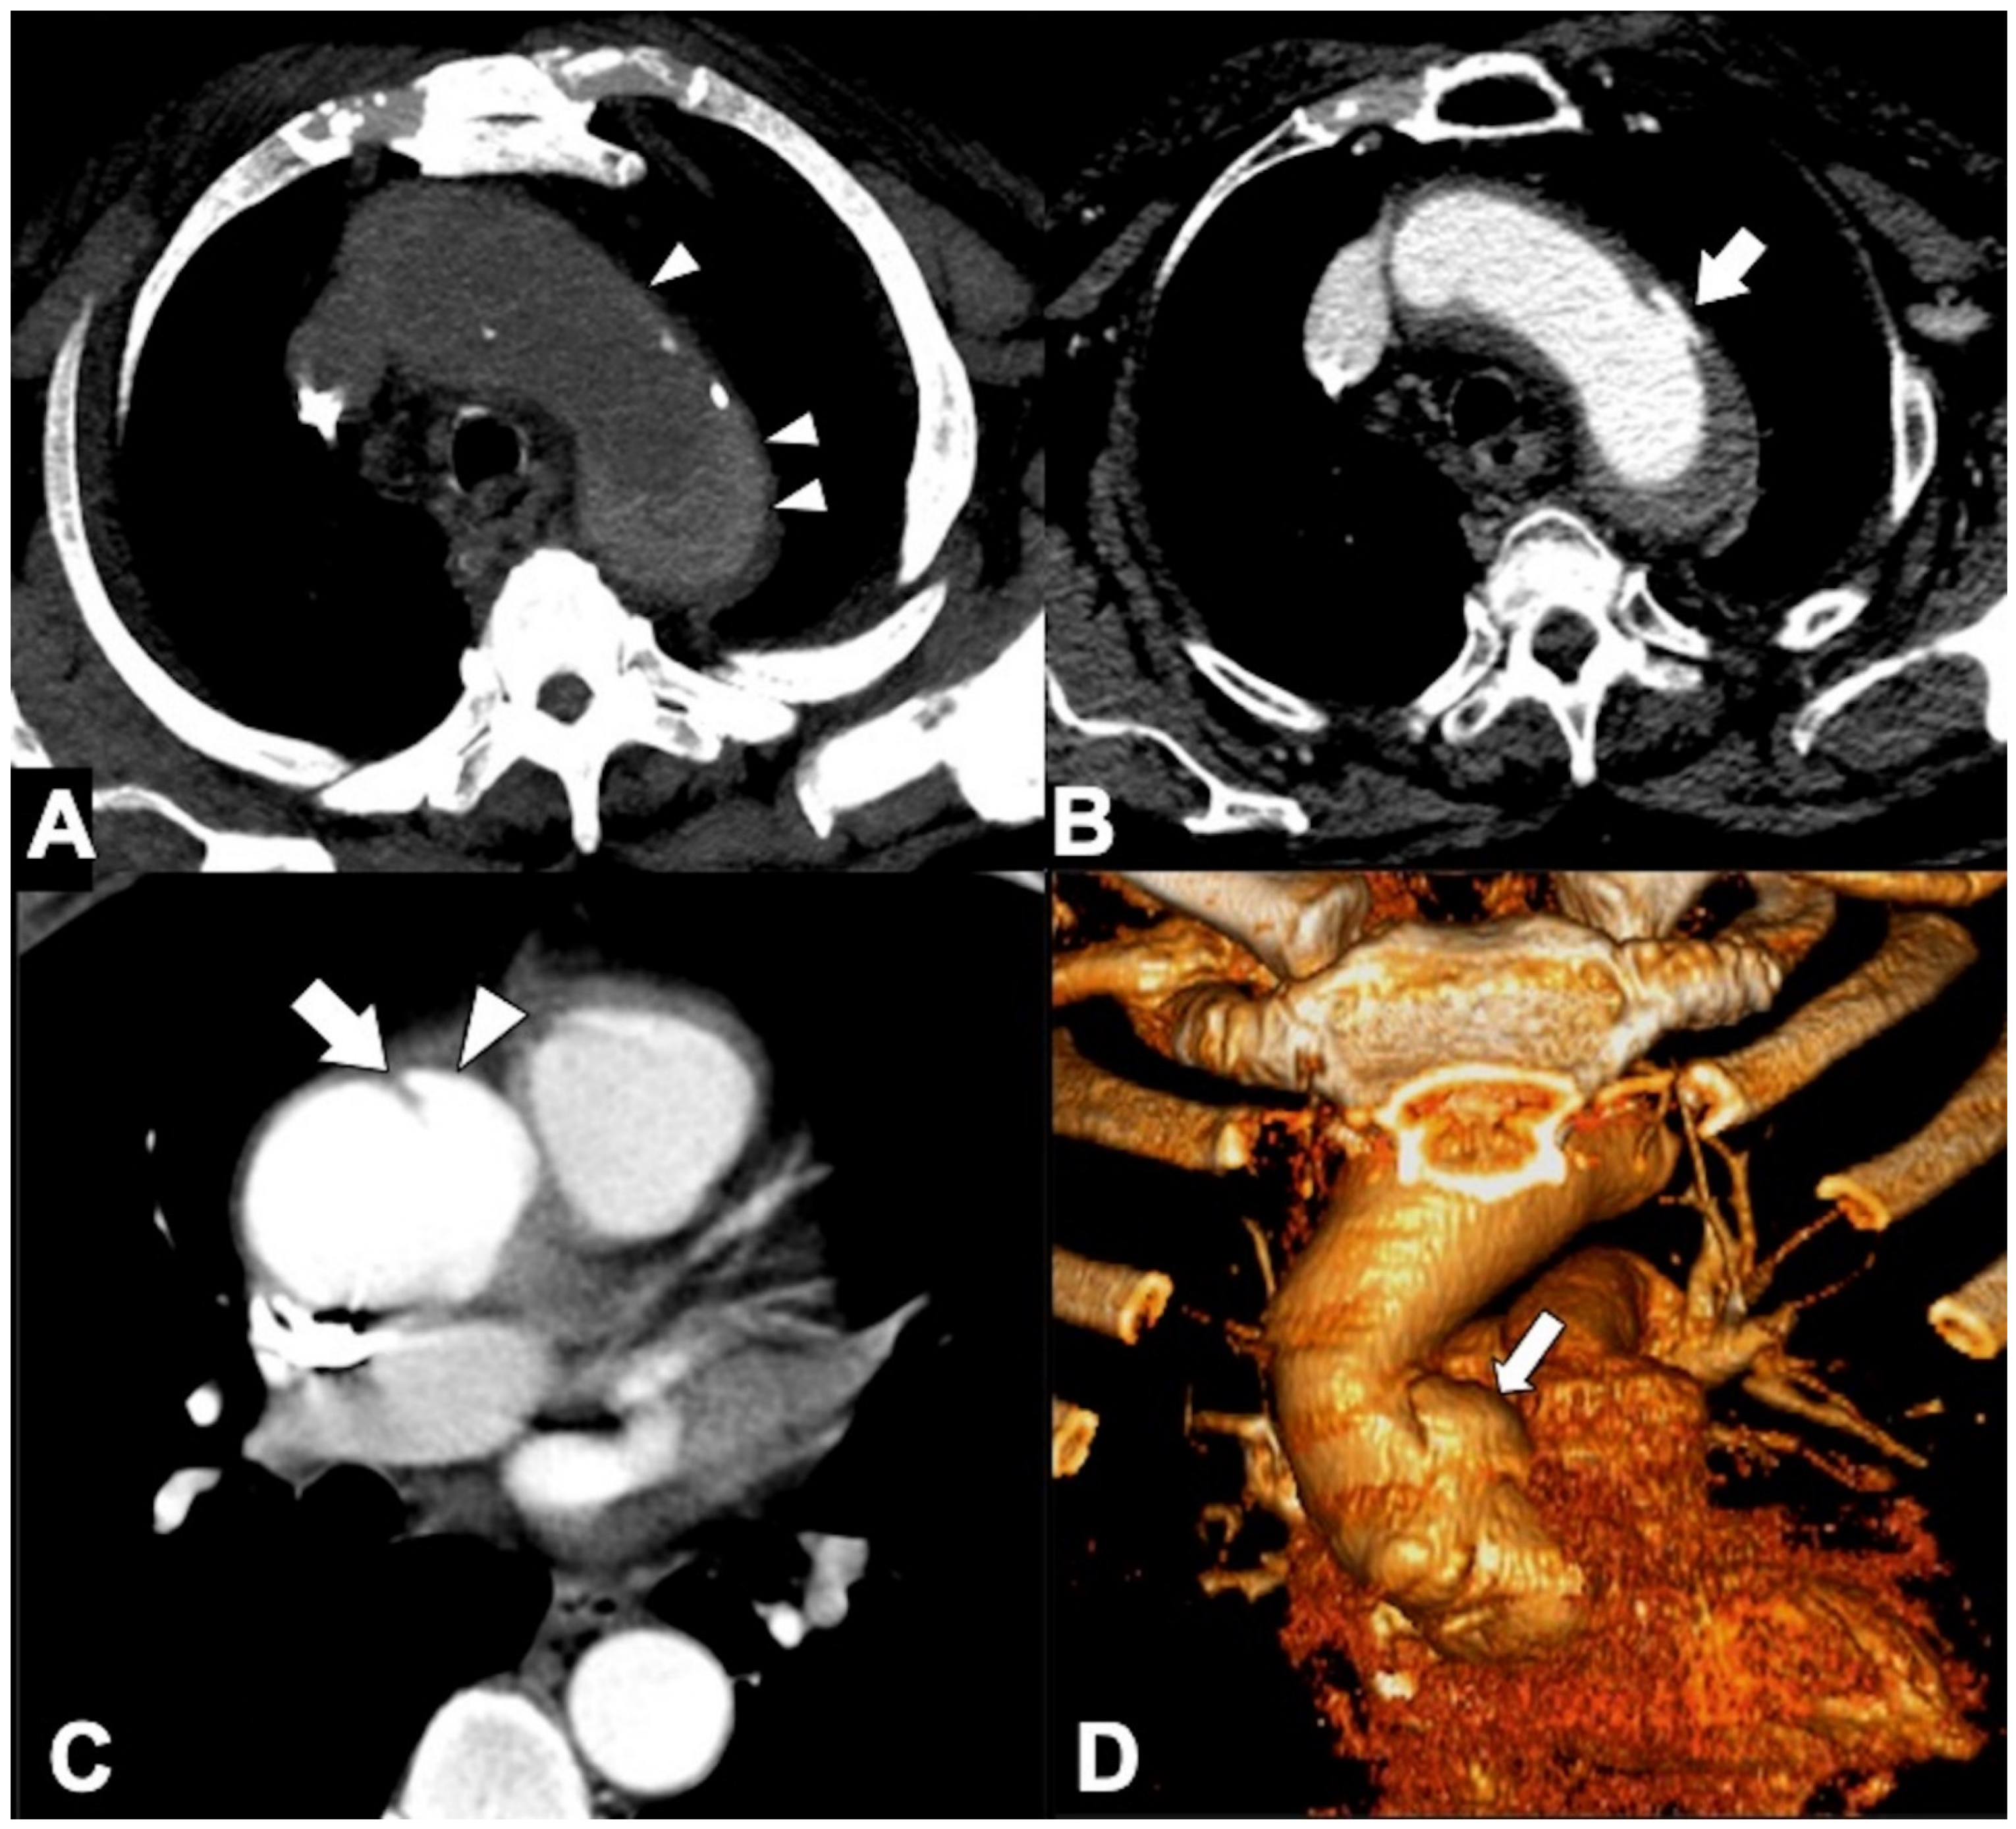

Because an abdominal aortic aneurysm occurs in 28% of patients with a TAA, it is important that the initial evaluation includes the entire thoracoabdominal aorta. TAAs are classified by location as affecting more commonly the ascending aorta (36%), aortic arch (34%), or DTA (30%) [103]. Annuloaortic ectasia is a condition with dilated sinuses of Valsalva along with effacement of the sinotubular junction (STJ) producing a pear-shaped ascending aorta commonly seen associated with Marfan syndrome and other connective tissue disorders (Figure 11A,B). The Crawford classification modified by Safi describes five types of thoraco-abdominal aortic aneurysms [104]. In the evaluation of TAA, CTA accurate depiction of aortic caliber on centerline imaging, morphology, relationship to the aortic arch vessels and the presence of thrombus or ulceration are of importance in deciding whether and how to intervene [104,105]. Accurately measured maximal aortic diameter is currently the primary metric used to guide surveillance strategy and the timing of surgical/endovascular intervention for patients with TAA (Figure 11C). The generally accepted aneurysm growth rate is 4 mm/year, and intercurrent dissection is associated with a more rapid growth rate. When the size of the aorta reaches its biomechanical “hinge point,” usually about 5.5 cm in diameter for ascending aorta and 7 cm for DTA, wall integrity rapidly declines, growth accelerates, and the incidence of complications rapidly increases. A rupture occurs when mechanical stresses on the wall exceed the wall strength, and as dictated by the law of Laplace, the rupture risk increases with aneurysmal size (Figure 11D) [106,107]. Clinical subtle and non-specific symptoms may already correspond to clear radiological signs of impending rupture. As far as the most accepted widespread criteria are represented by the maximum diameter and the expansion rate, there are other important imaging features that radiologists must be aware of, to promptly detect potentially life-threatening conditions (Table 6). These features are considered by most authors as signs of impending rupture (SIR) and include, amongst others, (1) a hyper-attenuating crescent sign, (2) focal wall discontinuity of circumferential calcifications (Figure 12A), (3) aortic bulges or blebs, and (4) a draped aorta sign or periaortic stranding [108,109]. These signs are mostly based on CT characteristics of the mural thrombus. Aneurysms are indeed often characterized by a thrombus lining the walls and by a patent lumen. As some authors consider the width of the mural thrombus a protective factor for aneurysm stability, the reduction in its width is considered a criterion of higher rupture risk [110]. Amongst the aforementioned SIR, the “hyperattenuating crescent sign” results from intraluminal blood creating a fissure that transits through the unstable mural thrombus to the intimal margin, forming a typical semilunar shape [111].

Figure 11. CTA of thoracic aorta aneurysms. (A) Marfan syndrome, a multisystem connective tissue disease caused by a defect in the protein fibrillin 1, and annuloaortic ectasia in a 42-year-old man. Sagittal MIP reconstruction image shows a proximal dilatation of the aortic anulus (1), sinuses of Valsalva (2) along with effacement of the STJ (4) producing a pear-shaped ascending aorta (3). (B) Axial CTA image shows sinuses ectasia in the same patient. In Marfan syndrome, a cut-off value of 5 cm of the ascending aorta diameter is recommended for surgical repair. (C) Axial CTA image shows a 12 cm ascending aorta aneurysm (asterisk) and a large mediastinal effusion. The risk of rupture of TAAs increases with size of the aneurysm according to Laplace’s law. (D) Axial CTA image shows a ruptured atherosclerotic aneurysm of the descending thoracic aorta. Note the high-attenuation fluid in the right pleural space, representing acute hemothorax (asterisk), and contrast medium extravasation from the aortic lumen (arrow).